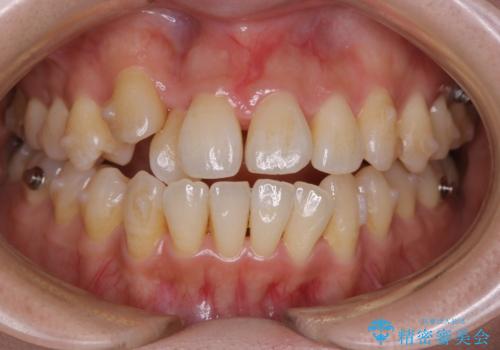

本来は外科ケース:インビザラインで前歯の重度がたつきとオープンバイトの改善

- 前歯のがたつきが気になるとご相談にいらした患者様です。矯正検査の結果、骨格的なズレが大きかったため当初の治療計画では外科矯正をご案内しました。ご本人が手術を望んでおらず、可能な限りの改善を目指すことを目標に治療を開始しました。

元々の骨格的なズレが大きかったため、当初は外科矯正をご提案していました。患者様の強いご希望により、非外科的な処置のみで可及的な改善を目指すことを目標に治療を行いました。以前よりもしっかり噛めるようになり、見た目も劇的に改善したことで大変ご満足いただけました。